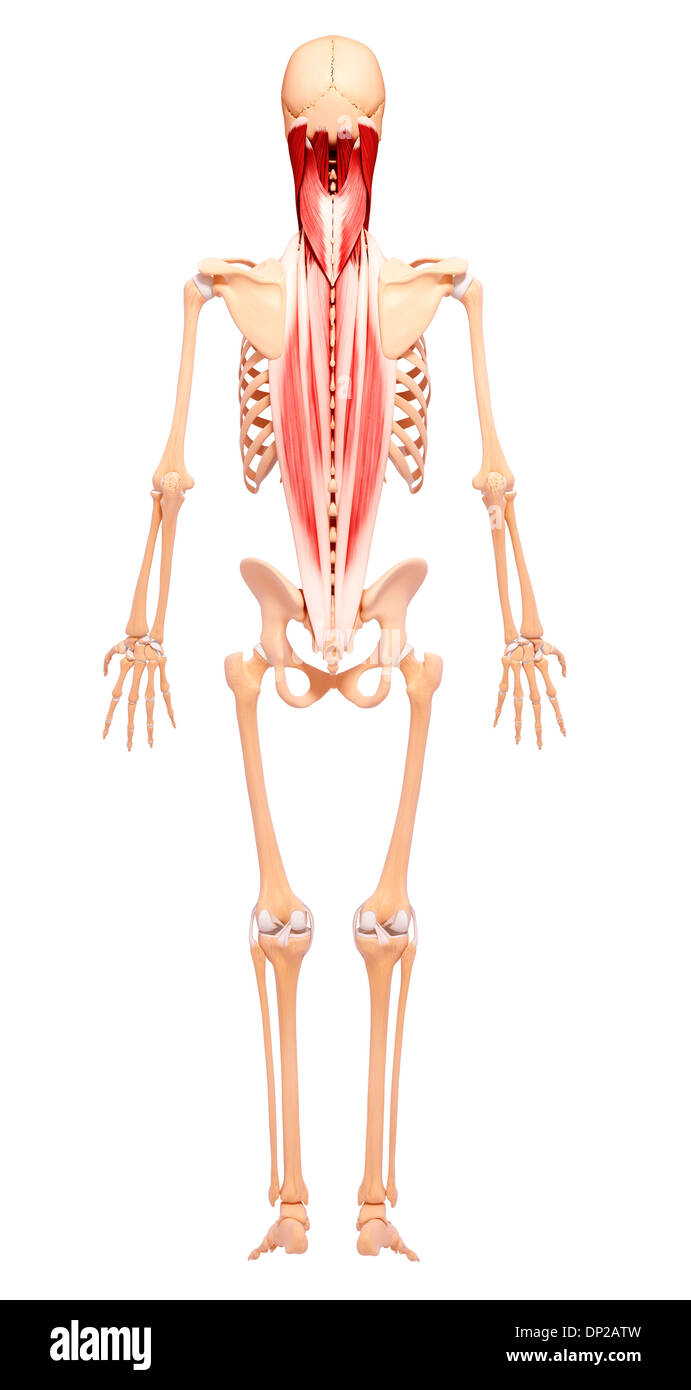

Les droits de l'Anatomy, artwork Banque D'Imageshttps://www.alamyimages.fr/image-license-details/?v=1https://www.alamyimages.fr/les-droits-de-l-anatomy-artwork-image65205977.html

Les droits de l'Anatomy, artwork Banque D'Imageshttps://www.alamyimages.fr/image-license-details/?v=1https://www.alamyimages.fr/les-droits-de-l-anatomy-artwork-image65205977.htmlRFDP2ATW–Les droits de l'Anatomy, artwork